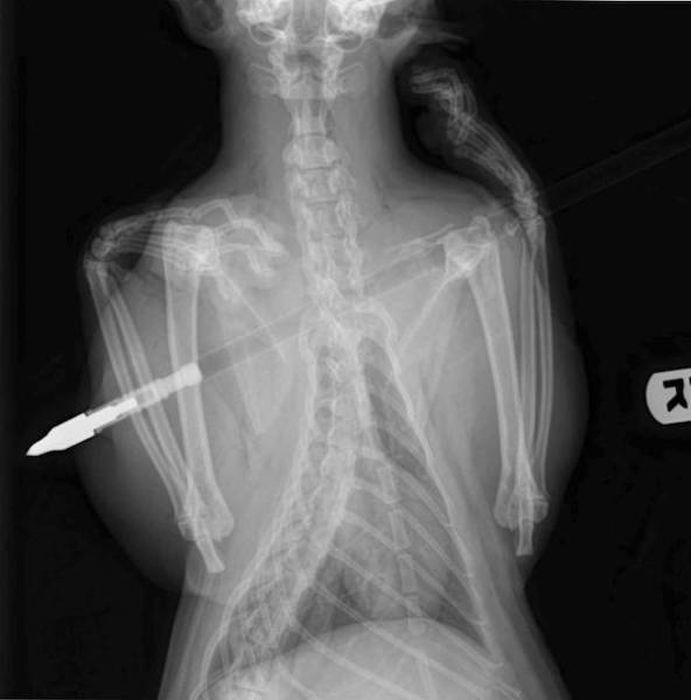

Предметы, которые не очень хочется видеть внутри себя

Под рентгеновскими лучами порой видны не только внутренние органы и кости, но и инородные тела, попавшие в организм

Истории попадания этих предметов в организм могут быть самыми невероятными и запутанными, но больше всего медиков интересует процесс их извлечения, впрочем, в этом заинтересованы и сами пациенты, допустившие нечто подобное со своим телом.